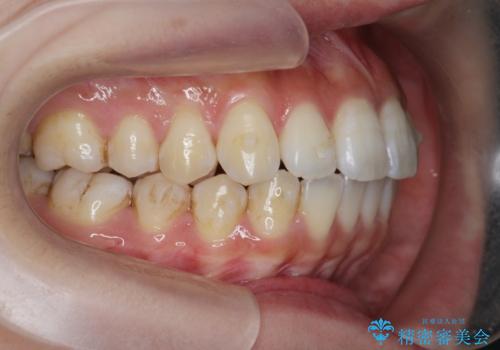

- 前歯の噛み合わせの開きの改善を求めて来院されました。

奥歯はほとんど動かさず(奥歯の噛み合わせはほとんど変えず)前歯のIPR矯正でガタつき前突感(出っ歯感)の改善を計画します。

ほとんど前歯のみの矯正治療であることからトータル14枚のマウスピースで並べるインビザラインライトによる治療を行います。